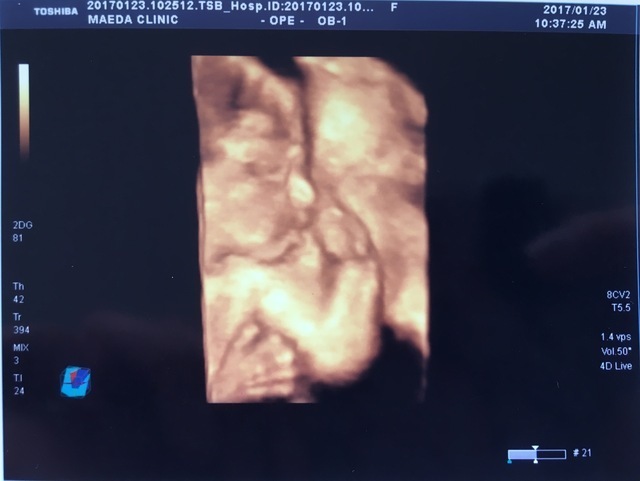

23週0日(23w0d・男の子)|☆あまちゃん☆ さん(27歳)

エコー写真撮影時のエピソード:

2回目の3Dエコー。しっかり横顔を見せてくれました‼︎ 何枚かあった中でファイティングポーズの様な写真。

3Dエコーで赤ちゃんの顔が見れたことによって、成長しているんだなーとうれしく思った記憶があります。生まれてからも手足をバタバタ、戦ってるようです!